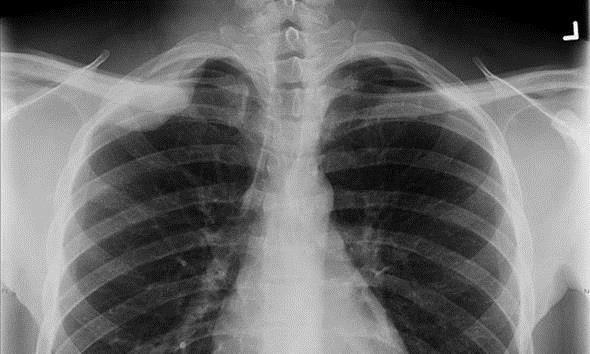

1895 - X ışını

İnsanlık tarihini değiştiren icatlar